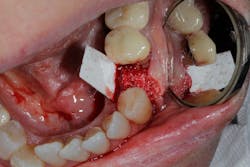

• Rebuild defects around adjacent teeth after extracting teeth due to periodontal disease (figures 5a–5c)

This surgical video demonstrates removal of a tooth with loss of buccal plate and grafting of the remaining socket with Geistlich Bio-Oss Collagen and Geistlich Bio-Gide to preserve the ridge for implant placement.